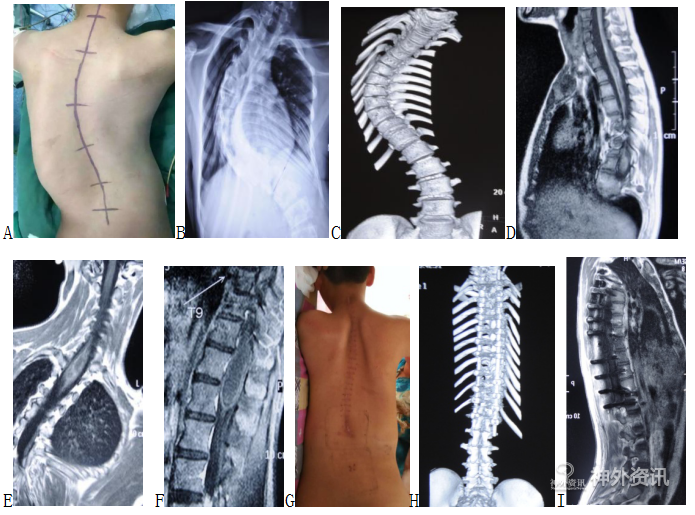

患者:男,14岁,因发现脊柱侧弯双下肢无力6年加重1年入院。

查体:脊柱右侧弯畸形,右侧剃刀背畸形。双上肢肌力V级,感觉未见异常。双下肢感觉,肌张力正常,双下肢肌力IV级。双侧髌阵挛、踝阵挛阳性。双侧膝腱反射、跟腱反射亢进。双侧巴氏征(+)。

立位平片示:脊柱右侧弯,Cobb角95°。

术前增强MRI:C7-T1、胸9-胸12可见脊髓增粗,可见增强信号,散在不均匀信号。下方可见脊髓空洞。

手术方式:胸背后正中入路肿瘤切除术+脊柱侧弯纠正术。

术中所见:完整取下C7-T2椎板,见硬脊膜膨隆,张力高,两侧悬吊后,正中剪开硬膜,两侧牵开,镜下见脊髓增粗,脊髓搏动差,沿后正中沟切开脊髓,探查见肿瘤位于C7-T1髓内,灰黄色,质地软,血供中等,边界欠清,与脊髓粘连紧密,周围见灰黄色陈旧出血,下方存在空洞。脊柱侧弯畸形仔细分离粘连,切除肿瘤大小约1.5*1*1cm。肿瘤切除后,彻底止血,严密连续缝合硬膜。咬除胸9-胸12后方棘突及双侧部分椎板,两侧悬吊后,正中剪开硬膜,两侧牵开,镜下见脊髓增粗,脊髓搏动差,沿后正中沟切开脊髓,探查见肿瘤灰黄色,质地软,血供中等,边界欠清,与脊髓粘连紧密,周围见灰黄色陈旧出血,下方存在空洞。仔细分离粘连,切除肿瘤大小约2.5*1.5*1.5cm。

A. 术前大体像;B. 术前立位平片;C. 术前三维CT重建;D. 术前MRI矢状位;E. 术前MRi冠状位;F. 术前MRI胸段;G. 术后大体像;H. 术后三维CT重建;I. 术后MRI矢状位。